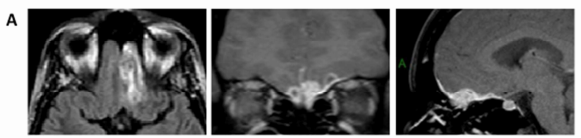

入院初期,医生考虑为炎症或感染性病变,遂行腰椎穿刺检查;脑脊液常规及生化均正常。但一个月后复查时,MRI里那团阴影膨胀了,病灶较前增大(图1B)。看东西重影,右侧眼眶也很痛。后续,又进行了微创活检,均无法确诊。

图1B

1个月后,MRI提示病灶体积略有缩小(图1C),我太开心了。由于病灶迅速缩小,所以我准备再等等。

图1C